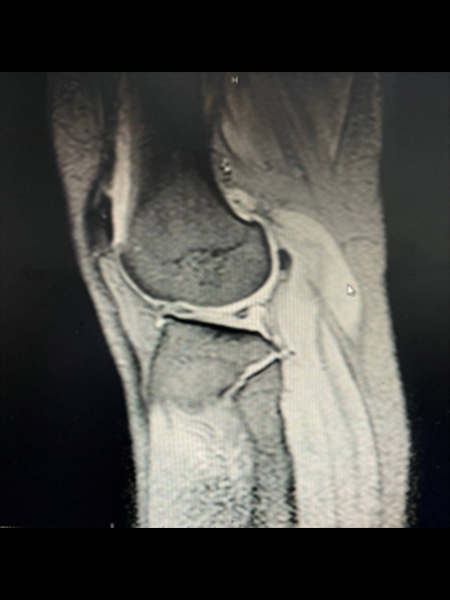

患者男、33岁,主诉在足球运动时扭伤膝关节,膝关节由屈曲位向伸直位,同时伴有扭转,此时由于关节周围的肌肉和韧带比较松弛,关节并不稳定,可造成半月板撕裂,引起膝关节疼痛、肿胀、活动受限,具有典型的关节交锁表现,后通过膝关节核磁共振检查得到证实。由于为半月板三度损伤,经过非手术治疗效果并不理想,而且关节交锁症状经常发生,导致关节积液、疼痛,影响正常生活。因此需要考虑手术治疗,建议患者尝试半月板缝合手术,尽量保留半月板完整性及功能。

在关节镜微创手术过程中,检查发现外侧半月板后角撕裂形成层裂,外侧半月板上层与下层分离,半月板后角稳定性变差,并且半月板表面毛糙。经过半月板锉新鲜化处理后,使用半月板缝合器进行缝合。根据半月板撕裂的程度缝合2针后,半月板稳定性得到恢复,半月板引起的关节交锁症状彻底消失。手术后使用铰链支具进行固定,逐渐增加膝关节屈曲角度,预防膝关节僵硬症状。此外,膝关节周围肌肉如股四头肌群发生严重萎缩,需坚持康复锻炼,恢复膝关节的稳定性。